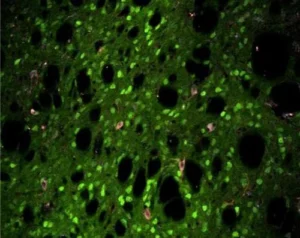

Προηγούμενες μεταθανάτιες μελέτες σε άτομα με σοβαρές μορφές της νόσου έδειξαν ότι υπήρξε μείωση σε ένα σπάνιο αλλά σημαντικό τύπο νευρώνα στο dorsal striatum, βαθιά μέσα στον εγκέφαλο. Μια ομάδα με επικεφαλής τον Christopher Pittenger, αναπληρωτή καθηγητή ψυχιατρικής, διερεύνησε αν η απώλεια αυτών των νευρώνων θα μπορούσε να προκαλέσει τα συμπτώματα.

Αφαίρεσαν περίπου τους μισούς από αυτούς τους σπάνιους νευρώνες (που φαίνονται με κόκκινο χρώμα στη συνοδευτική εικόνα), οι οποίοι χρησιμοποιούν τον νευροδιαβιβαστή ακετυλοχολίνη, από το dorsal striatum εγκεφάλου ποντικών. Αυτά τα ποντίκια εμφάνισαν κινήσεις που μοιάζουν με τικ όταν υποβάλλονταν σε στρες ή όταν εκτέθηκαν σε αμφεταμίνη, δύο καταστάσεις που μπορούν επίσης να εμφανίσουν τικ σε ασθενείς.

Ωστόσο, άλλα συμπτώματα που παρατηρήθηκαν στο σύνδρομο Tourette, όπως τα προβλήματα με τη μάθηση, των κινητικών δεξιοτήτων και το φιλτράρισμα των αισθητηριακών πληροφοριών, δεν επηρεάστηκαν. Αυτό υποδηλώνει ότι η απώλεια αυτών των ειδικών νευρώνων μπορεί να είναι επαρκής μόνο για την παραγωγή τικ, αλλά όχι και των άλλων συμπτωμάτων που παρατηρούνται στο σύνδρομο Tourette, λένε οι ερευνητές.